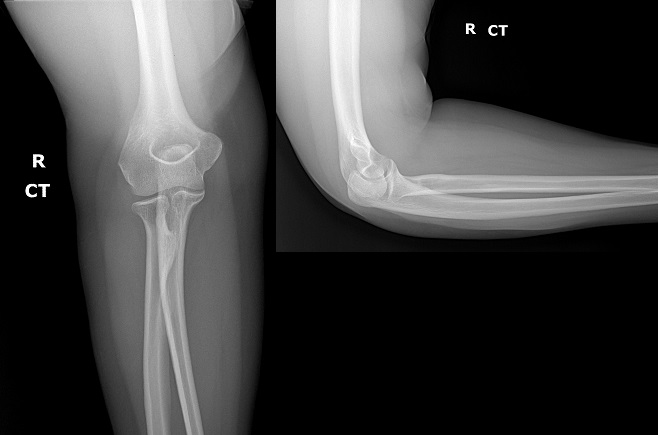

An 80 year old female presents to your office with a left ring finger deformity after a fall one week ago. She initially went to urgent care and xrays were unremarkable for a fracture (Figures 1 and 2). A photo of her left ring finger is shown in figure 3. On physical exam the left ring finger is in hyperextension at the PIP joint and flexion at the DIP joint. She able to flex her PIP joint with full motion. What is the best treatment option?